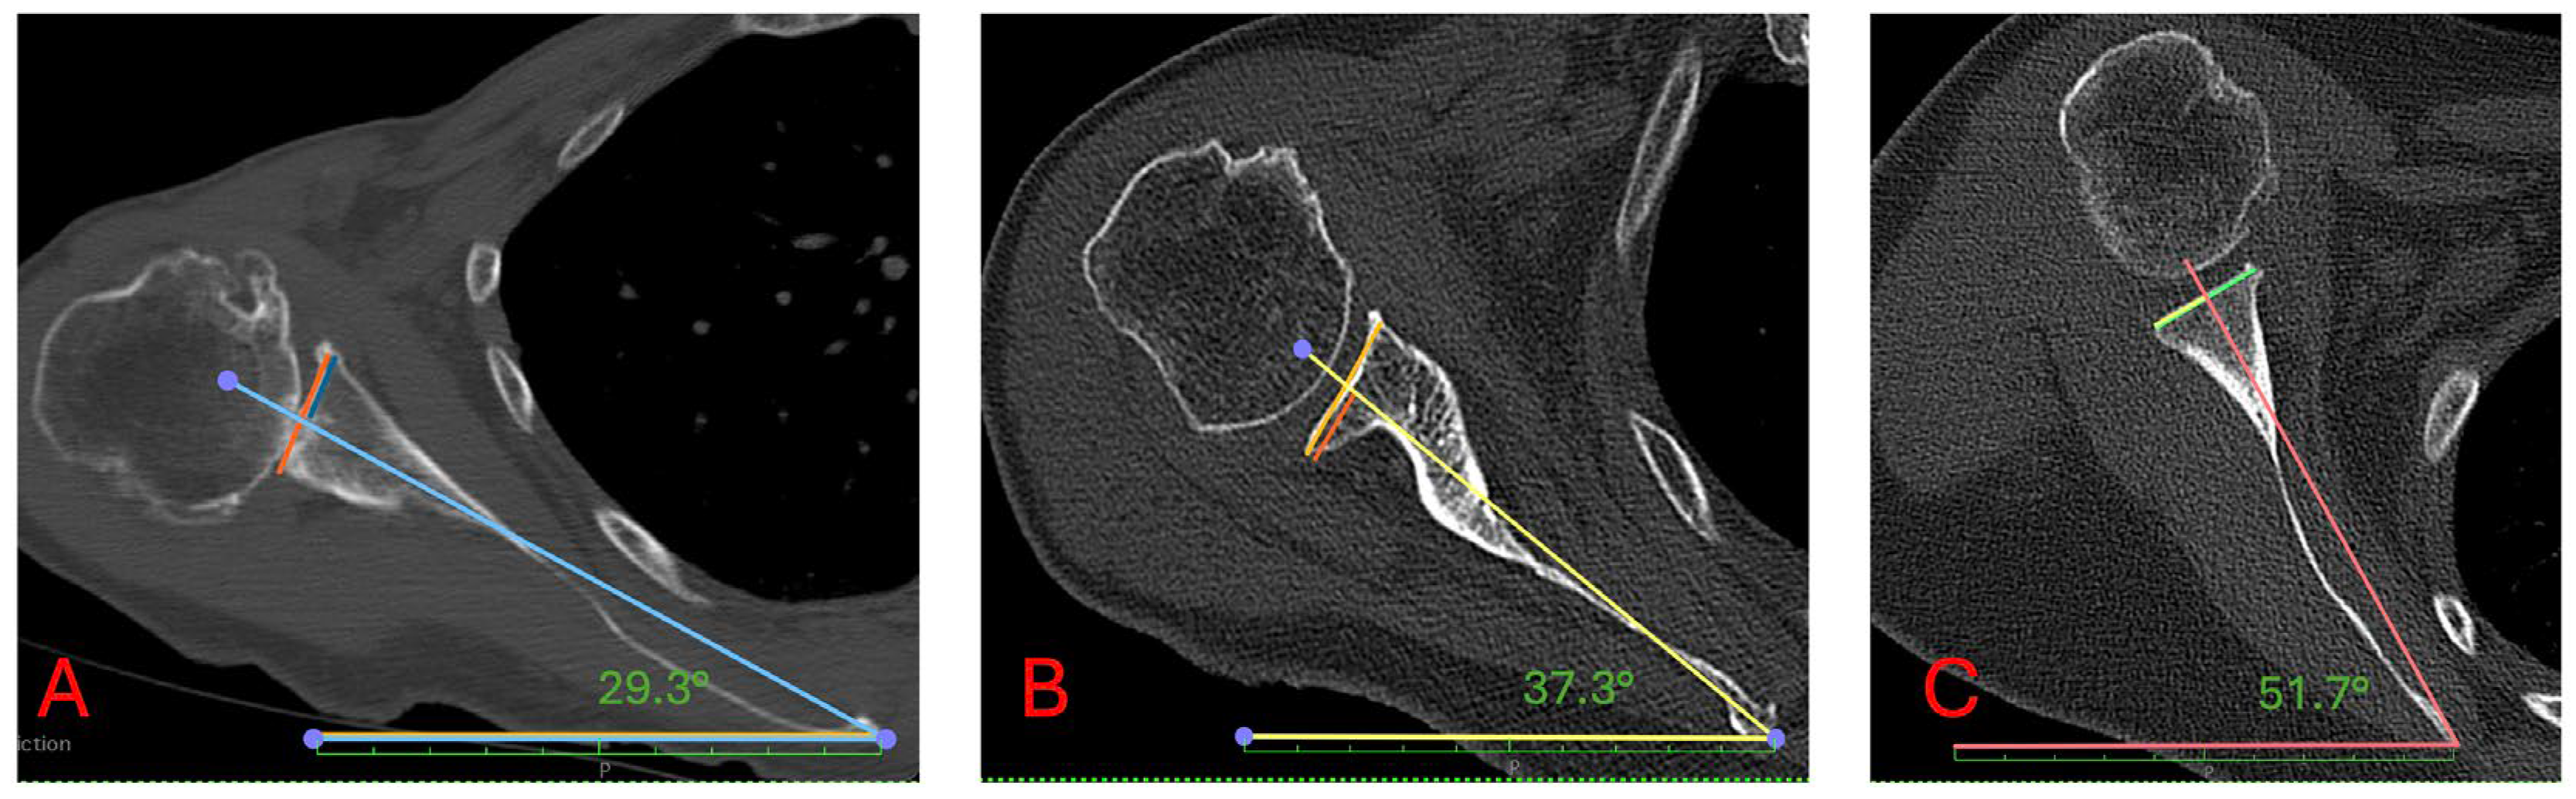

2.1. Radiological Analysis

| Cobb Angle | Scapular Internal Rotation | Anterior Scapular Tilt |

|---|---|---|

| 40.7 (12.4) | 41.9 (8.4) | 24.1 (13.3) |

| Cobb Angle | Scapular Internal Rotation (Mean (SD)) | p-Value | Anterior Scapular Tilt (Mean (SD)) | p-Value |

|---|---|---|---|---|

| ≤36 | 40.3 (9.3) | 0.047 | 25.8 (13.0) | 0.570 |

| >36–46 | 41.8 (7.8) | 23.3 (12.5) | ||

| ≥47 | 43.7 (8.0) | 23.5 (14.8) |